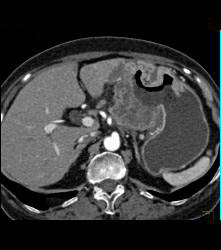

Antral Carcinoma